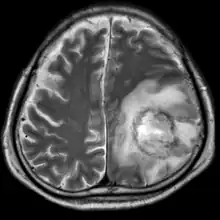

| T2-weighted MRI showing a necrotic brain absess as a result of GAE caused by an infection of Acanthamoeba, genotype T18 | |